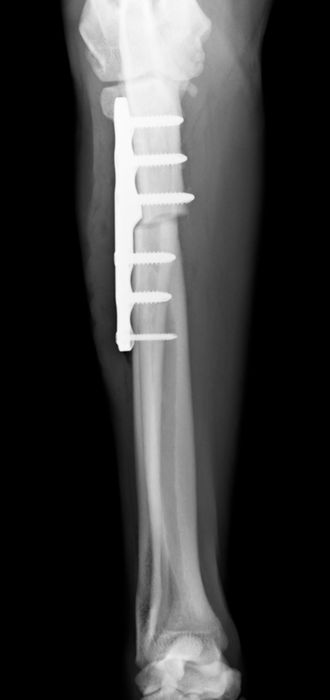

●骨プレート

ステンレス製もしくはチタン製の金属の板(プレート)と骨ネジ(スクリュー)を使用して固定を行います。

●髄内ピンと骨プレートの併用(プレート-ロッド併用法)

骨折・脱臼治療における最小侵襲手術(MIS)について

骨折治療における最小侵襲手術(minimally invasive surgery MIS)

MISは、人医療では20年以上前から提唱されているコンセプトですが、軟部組織(皮膚や筋肉など)の侵襲を最小限にし、骨折部に対してもよけいな侵襲を加えないことで骨折治癒を促進させる方法です。近年、獣医療領域でも実施されるようになってきました。

当院では、症例に応じて創外固定法によるMISや最小侵襲骨接合術(minimum invasive plate osteosynthesis MIPO)を実施しています。

※単純骨折に対するプレート固定はopen reduction internal fixationを行っています。